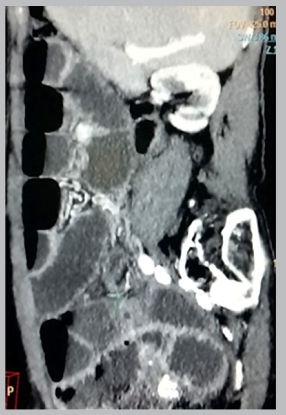

Laboratory tests showed 7590 leukocytes/mm3 with 89.1% neutrophils. On admission, an abdominal X-ray (figure 1) demonstrated pneumatization and dilated small bowel loops characteristic of abdominal obstruction. The CT scan also showed dilated bowel loops and air-fluid levels (figure 2-A and 2-B). The patient subsequently was admitted with the diagnosis of bowel obstruction. Nine hours after admission she developed leucopenia 860/mm3 with 45.3% neutrophils and a C-reactive protein (CRP) of 190.80 mg/L. Thirty-three hours after admission, the clinical picture worsened, with greater abdominal distention accompanied by 1460/mm3 leukocytes, 55.5% neutrophils, a CRP of 216.7 mg/L, and a procalcitonin (PCT) of 4.42 ng/mL.

Figure 2-A - Abdominal Computed Tomo- graphy, coronal view. Dilation of small bowel loops due to obstruction

Figure 2-B - Abdominal Computed Tomogra- phy, sagital view. Dilation of small bowel loops and air-fluid levels